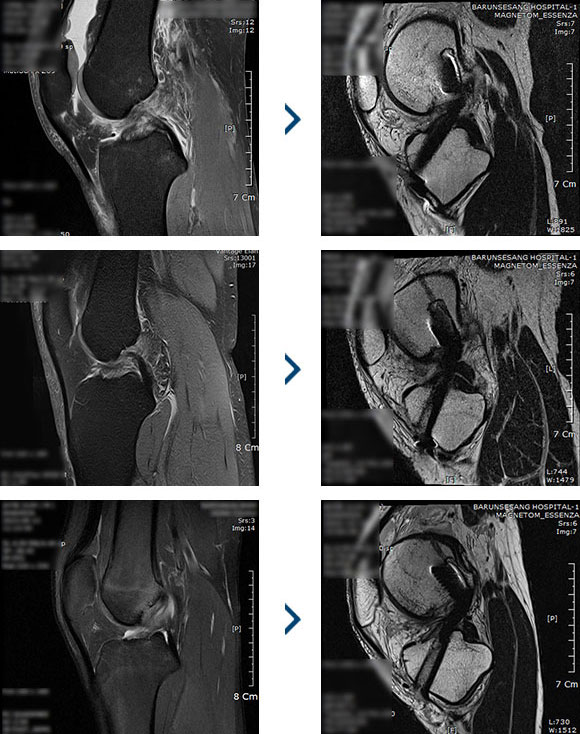

다양한 수술/비수술의

인대 재건술은 관절의 인대가 손상되었거나 파열되었을 경우 시행하는 수술법입니다. 전방/후방십자인대, 내/외측 측부인대 등 무릎 관절이 외부 충격이나 손상으로 제 기능을 상실한 경우 새로운 인대를 이식하여 원래의 기능을 되찾아주는 방법입니다. 인대 파열 시 발생하는 인대 강도의 약화, 길이 변화에 대해 가장 확실하게 본래의 기능을 회복시켜주는 수술입니다.

무릎 전방십자인대의 손상 및 파열된 환자

무릎 후방십자인대의 손상 및 파열된 환자

1. 관절경을 이용하여 인대의 위치와 손상 정도를 확인하고, 파열된 인대를 정리합니다.

2. 인대가 삽입될 터널 만들기 - 대퇴골과 경골에 이식건을 삽입할 구멍을 만듭니다.

3. 인대삽입 - 터널 구멍에 이식건을 통과시켜 연결 후 양쪽 뼈에 이식건을 고정하여 재건합니다. 타가건을 이용할 경우 잔존 인대조직을 덧대어 이식함으로써 회복을 앞당기고, 더욱 튼튼하게 재건되도록 돕습니다.